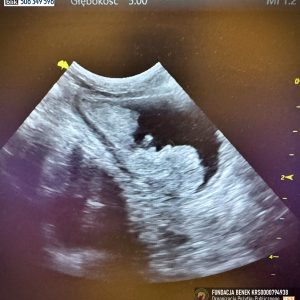

w obrazie usg typu a-fast – hiperechogenne, okrągłe zmiany w tkance wątrobowej – podejrzenie guzkowego rozrostu nienowotworowego wątroby – do potwierdzenia w badaniu FNA, zmiana w pęcherzu moczowym dosyć nieregularna o wymiarach ok. 2,5 x 1,3 cm, nerki o zatartej strukturze korowo-rdzennej poza tym brak odchyleń